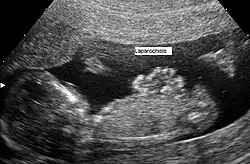

Wrodzony rozszczep powłok brzusznych widoczny w obrazie USG płodu.

Wytrzewienie (łac. gastroschisis, ang. gastroschisis) – wada rozwojowa, zazwyczaj izolowana, polegająca na wrodzonym rozszczepie powłok brzusznych.